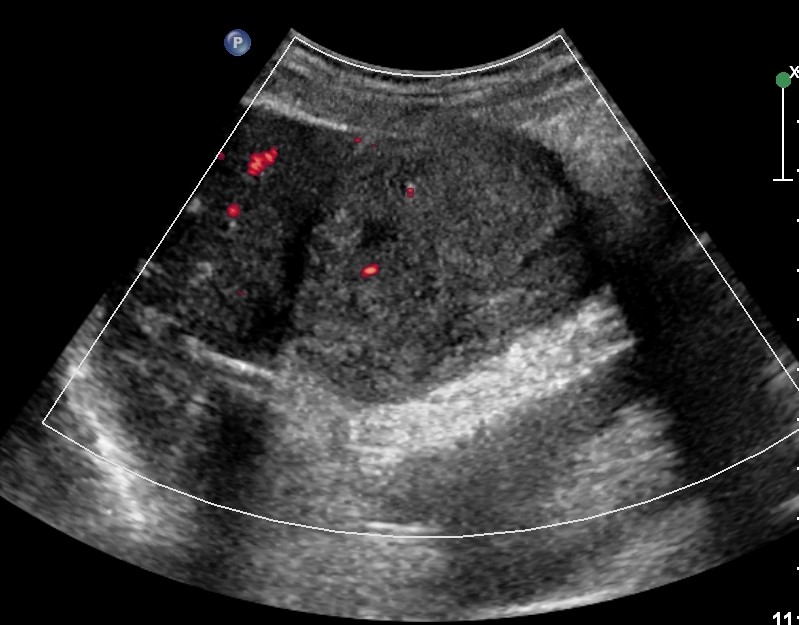

GB & BD ) лӢҙлӮӯ м„қнҡҢлҸҷл°ҳ 충мӢӨм„ұ л¶Ҳк· м§Ҳ лҸҷл“ұм—җмҪ” мў…кҙҙ |

2019.05.11 мЎ°нҡҢмҲҳ: 203 |